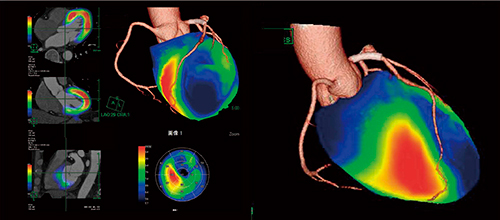

図8 心筋シンチグラフィと3D-CTのフュージョン画像